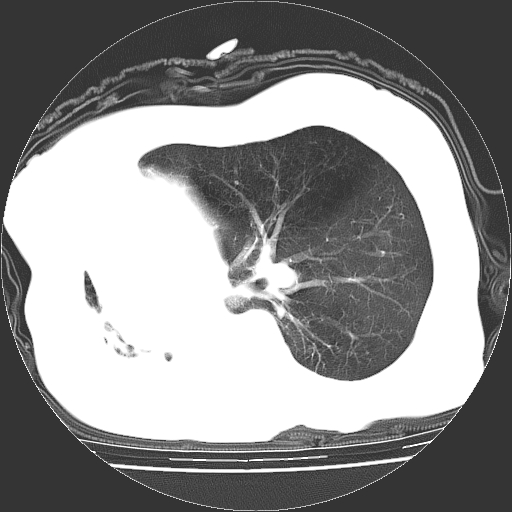

标题: CT23991:女,72岁,咳嗽、憋气一周。 [打印本页]

女,72岁,咳嗽、憋气一周,十年前曾患肺结核及胸膜结核。

右侧毁损肺,右侧纵隔疝

右侧毁损肺,右侧纵隔疝,左肺代偿!

1.右侧损毁肺伴胸膜钙化,2.左肺小结节灶,良性可能大,注意复查。3.肝脏左叶囊肿。4.先天性一侧肺不发育待出外(右侧胸廓无明显塌陷)。对比原片应该非常有帮助。